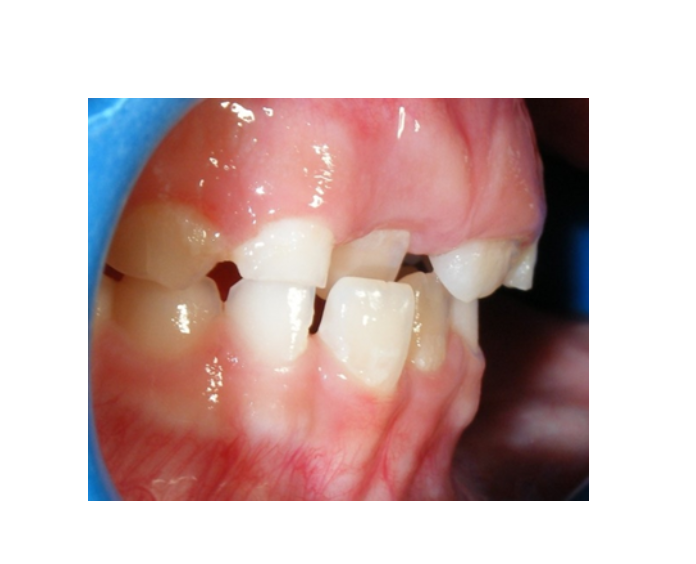

Mordida Cruzada anterior unidental